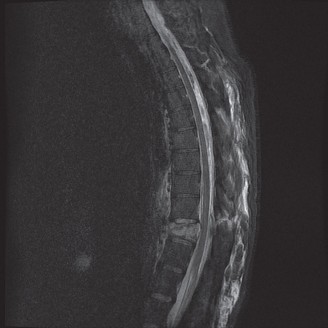

When surgical intervention becomes unavoidable, meticulous pre-operative planning is the cornerstone of a successful outcome. Advanced imaging is non-negotiable. An MRI with and without gadolinium contrast is the gold standard for defining the extent of the epidural abscess, the degree of neural compression, and the involvement of adjacent paraspinal musculature (e.g., psoas abscess). T1-weighted images typically show hypointense signals in the infected marrow, while T2-weighted and STIR sequences reveal hyperintense fluid and edema in the disc space and vertebral bodies. Gadolinium enhancement highlights the vascularized inflammatory phlegmon and the capsule of any abscesses.

To contextualize the decision-making algorithm, consider the classic presentation of a middle-aged patient with multiple medical comorbidities. A paradigmatic case involves a 48-year-old obese female (Body Mass Index of 43) with poorly controlled diabetes mellitus who presents with severe, unrelenting low back pain, fevers, and chills. Advanced imaging, specifically magnetic resonance imaging (MRI), typically demonstrates discitis involving the L4–5 disc space with adjacent osteomyelitis of the L4 and L5 vertebral bodies. Crucially, in many early or medically responsive cases, there is an absence of epidural abscess formation, and standing radiographs reveal relatively normal sagittal and coronal alignment. When such a patient is neurologically intact—lacking saddle anesthesia, bowel/bladder incontinence, or upper motor neuron signs—the immediate clinical imperative shifts from urgent surgical decompression to aggressive pathogen identification and targeted antimicrobial therapy.